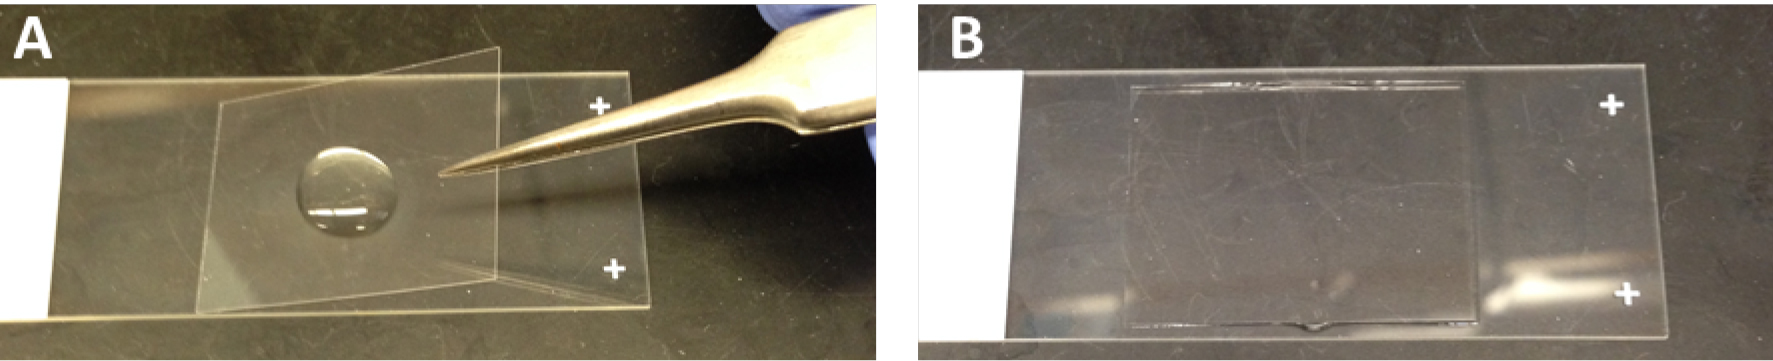

Lung sectioning and staining are essential methods for studying lung development or lung pathology. Immunofluorescent staining visualizes the expression and localization of interested proteins. H&E staining is most widely used in histology studies and medical diagnosis. Masson’s trichrome staining detects collagen deposition in tissues. Figure 2 shows representative images of each staining on the lung sections from mice that had been undergone bone marrow transplantation and then infected with murine gamma herpesvirus 68 for three weeks.

Figure 2. Lung section staining. The lungs were removed from C57BL/6 mice that had undergone transplantation of syngeneic EGFP-expressing bone marrow for 5 weeks, and followed by infection with murine gamma herpesvirus 68 (5 x 104 pfu/mouse) for 3 weeks. The lung had developed pneumonitis and pulmonary fibrosis as evidenced by infiltration of immune cells and deposition of collagen. A. Lung section is immunofluorescent stained with rabbit anti α-smooth muscle actin (α-SMA) antibody and α-SMA positive cells are visualized by Texas Red conjugated goat anti-rabbit IgG antibody in red. Donor bone marrow-derived cells express EGFP in green. DAPI counterstains all of the cell nuclei in blue. B. H&E staining colors cytoplasm pink and nuclei blue; C. Masson’s trichrome staining colors collagen blue, cytoplasm pink and nuclei dark brown to black.